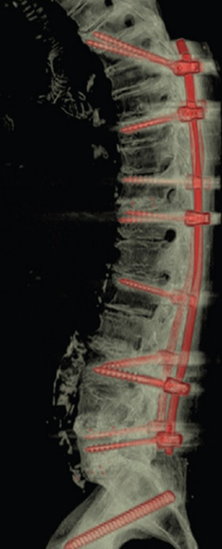

图36 多棒固定向两棒固定的过渡

图37 半坚强固定